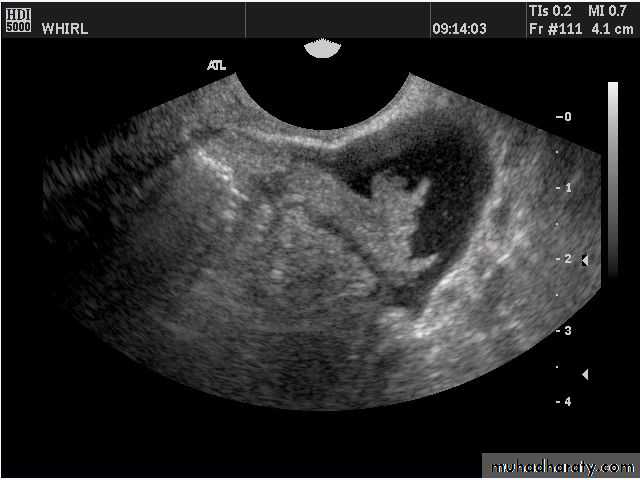

Images from women with differing expressions of the four major subtypes of the metabolic syndrome associated with polycystic ovary syndrome (A–D). The images exhibit quite differing ultrasonographic appearances in the size and distribution of follicles within PCOS ovaries. A recent corpus luteum is clearly visible in the ovary in panel (D).

Images from women with differing expressions of the four major subtypes of the metabolic syndrome associated with polycystic ovary syndrome (A–D). The images exhibit quite differing ultrasonographic appearances in the size and distribution of follicles within PCOS ovaries. A recent corpus luteum is clearly visible in the ovary in panel (D).• POLYCYSTIC OVARY SYNDROME